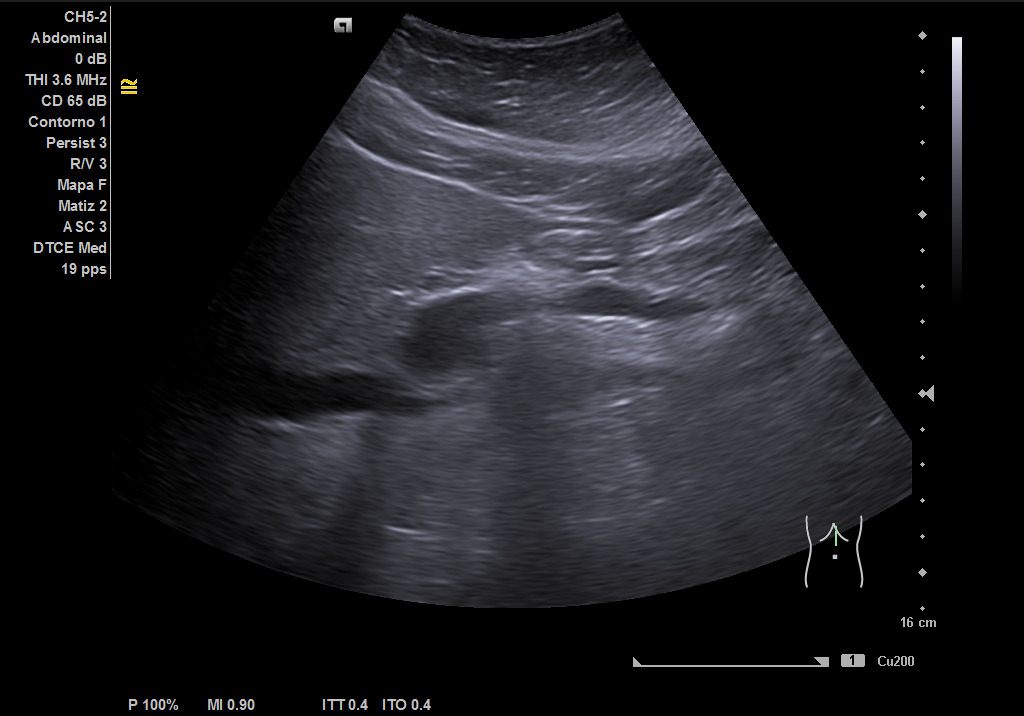

Ecografía clínica: hígado de tamaño y contornos conservados, con aumento difuso de la ecogenicidad, sin presencia de lesiones focales en las porciones visualizadas. Vesícula biliar alitiásica de tamaño y paredes normales. Vía biliar no dilatada. Imagen redondeada de 36,5 mm hipoecoica homogénea que muestra flujo con el Doppler que corresponde con porta extrahepática. Páncreas parcialmente visualizado sin alteraciones valorables. Bazo de tamaño conservado. Ambos riñones normoposicionados, de tamaño y grosor cortical conservados con buena diferenciación corticosinusal. Vejiga replecionada de paredes lisas. No líquido libre intrabdominal. Imagen redondeada de 36,5 mm hipoecoica homogénea que muestra flujo con el Doppler que corresponde con porta extrahepática. Conclusión: esteatosis hepática grado II, imagen redondeada de 36.5mm hipoecoica homogénea que muestra flujo con el Doppler que corresponde con porta extrahepática.

Ecografía: esteatosis hepática moderada e imagen altamente sugestiva de aneurisma de la vena porta extrahepática, permeable y de unos 39 mm aproximadamente.

Aneurisma de vena porta extrahepática.